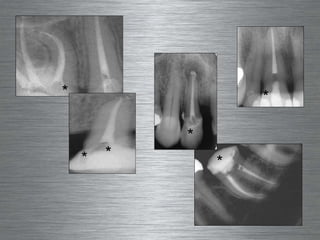

Treated with Rotary  Nickel Titanium Files Flat Canals * * Will look great on the radiograph

Treated with Rotary  Nickel Titanium Files Canals with a  “ Tear-Shaped” Cross Section * * Will look great on the radiograph

This may explain the  frequently encountered enigma : Endodontic  failures  in roots with apparently  good root canal fillings * * Misleading  2D  X-Ray images